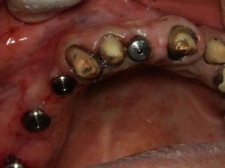

Implantes con el Muñón Protésico

Tornillos de Cicatrización